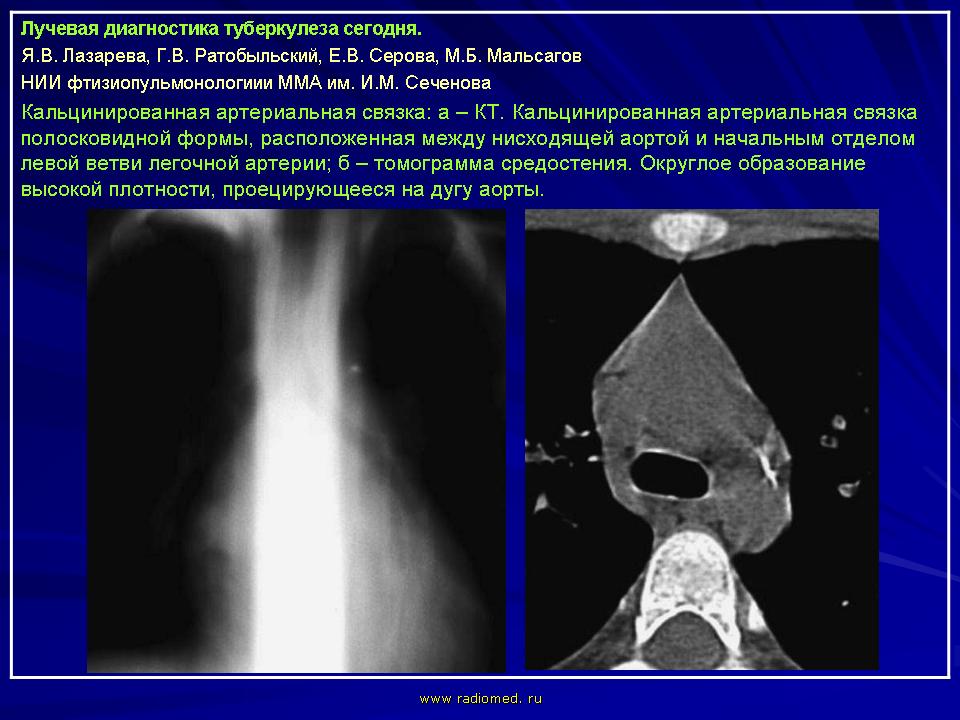

Лучевая диагностика туберкулеза сегодня

Я.В. Лазарева, Г.В. Ратобыльский, Е.В. Серова, М.Б. Мальсагов

НИИ фтизиопульмонологиии ММА им. И.М. Сеченова